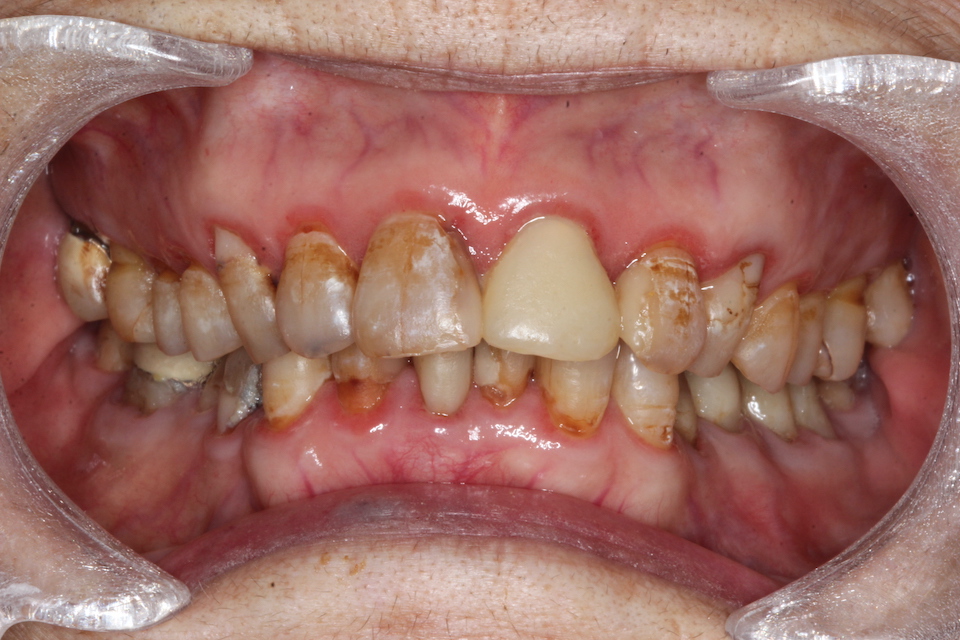

87歳

3年毎の画像を遡って見てみましょう。